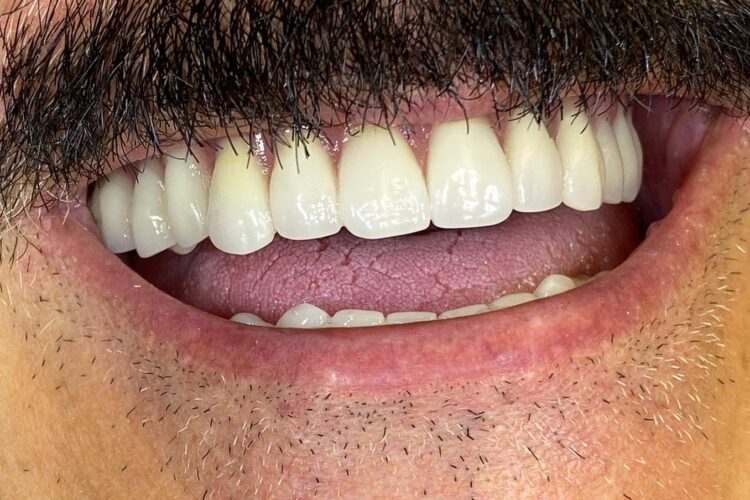

Caz reabilitare implanto-protetica

Pacient in varsta de 68 ani, s-a prezentat in clinica noastra cu cerinta stricta de a avea o lucrare fixa desi era edentat subtotal,  iar dintii restanti aveau indicatie de extractie. I s-a propus ca plan de tratament o protezare fixa pe implanturi. Planul de tratament a inclus 8 implanturi la maxilar si 6 la mandibula care vor fi finalizate prin lucrari protetice insurubate din zirconiu. Pana la finalizarea lucrarilor definitive, pentru realizarea unor lucrari echilibrate ocluzal i s-a propus si realizat temporizare prin lucrari de PMMA.